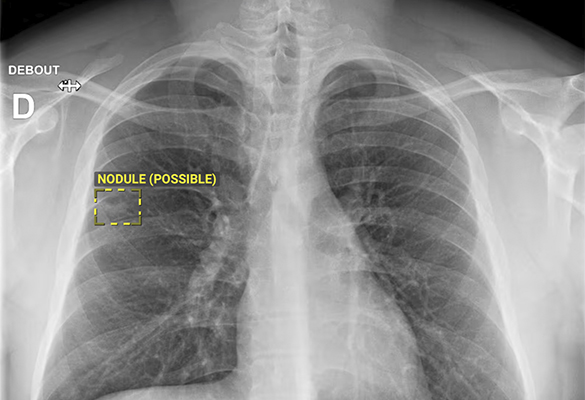

A tecnologia processa automaticamente as imagens, sinalizando zonas com probabilidade de lesões ósseas ou pulmonares. O médico pode, assim, integrar essa informação na sua observação clínica e atuar de forma mais célere e fundamentada.

O ChestView, por sua vez, identifica alterações no tórax, como pneumonias, derrames pleurais, pneumotórax e nódulos, em todos os utentes a partir dos 15 anos de idade.